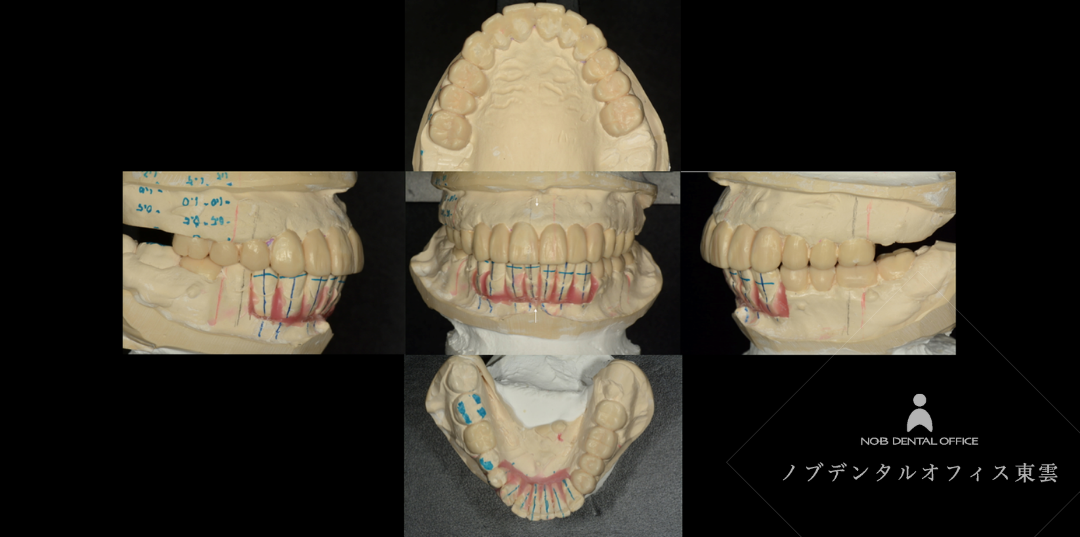

また、診察用の模型を作成し、患者様と担当医で治療のゴールを可視化しました。

歯並びと噛み合わせを再現する模型

診断用ワックスアップと呼ばれる模型です。

治療後の状態を模型にして、カウンセリング時に見ながらお話しします。